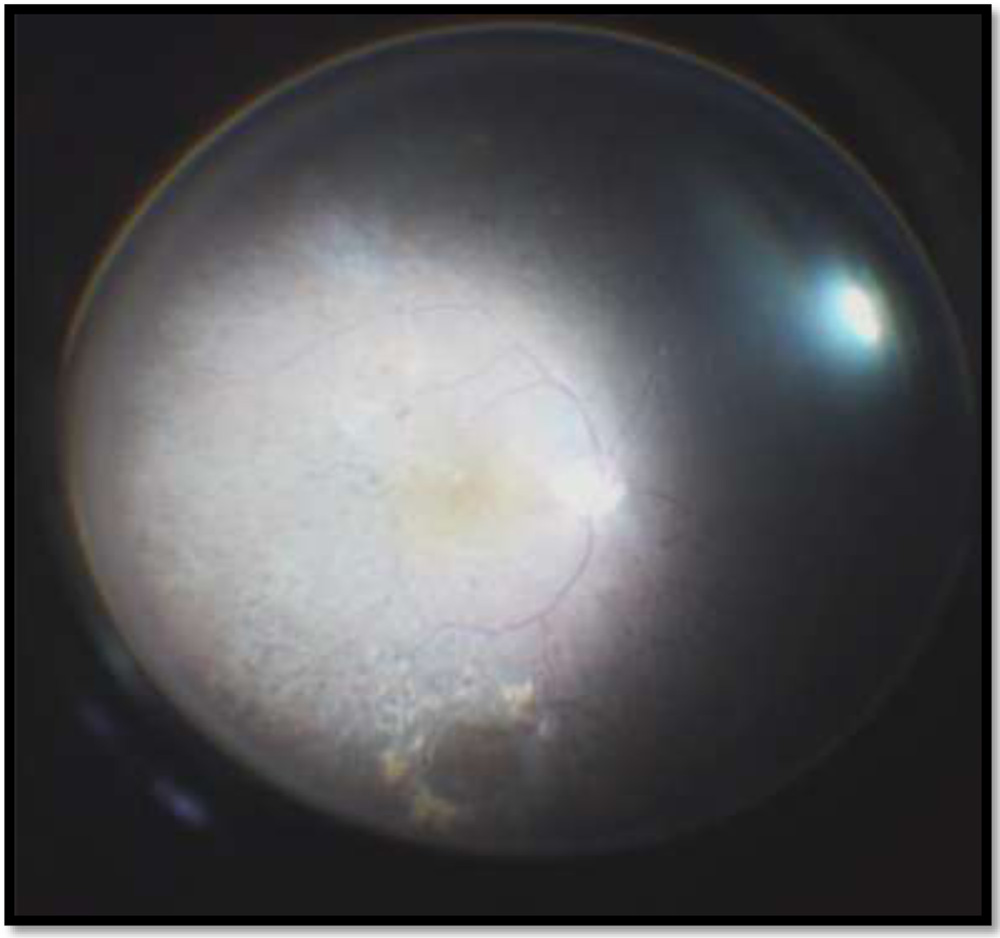

FIGURE 7: View with 132D lens in fluid filled eye